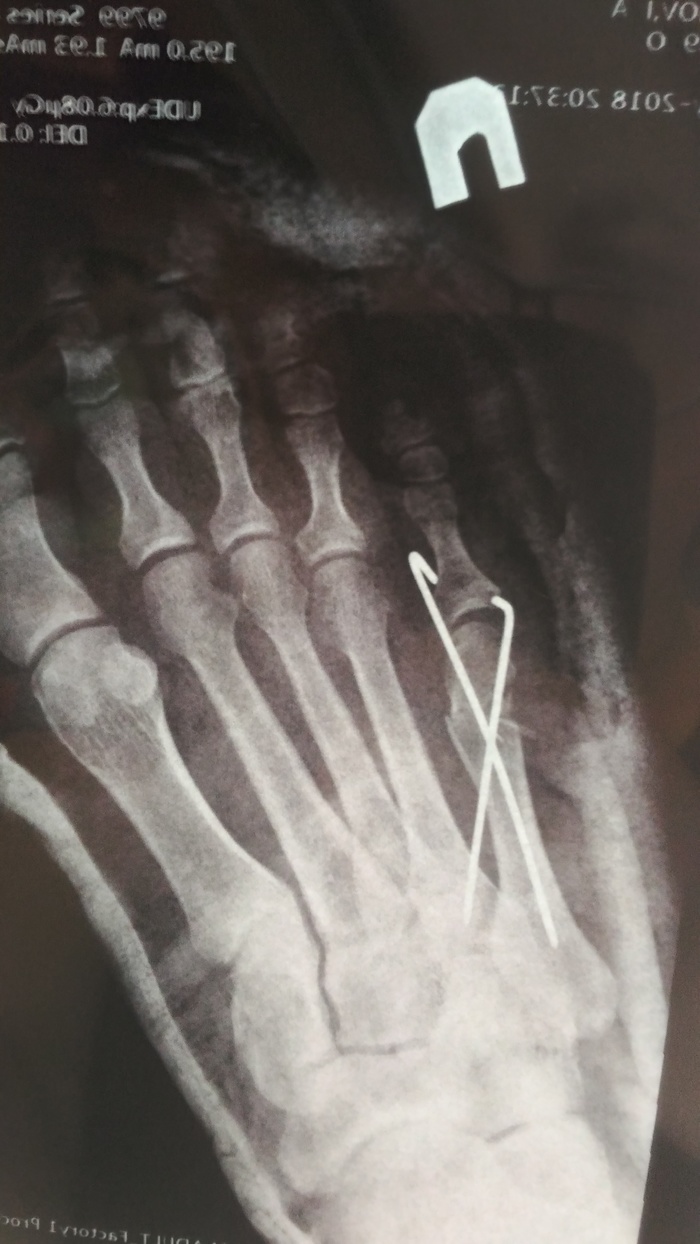

28 мая мой братик 40 лет от роду решил поиграть в бадминтон и сломал себе ногу, а точнее пятую плюсневую кость. В травмпункт мне удалось затащить его только 31 мая и то с трудом, так как я на 11 лет младше и давление на него оказывать сложновато. Там сделали снимок

и сказали срочно ехать в приемный покой во Вредена что бы там делали репозицию и иммобилизацию))) проще говоря что бы как то зафиксировать косточки с отломками и наложить лангету.

Во Вредена предложили три варианта поставить либо спицы, либо пластину либо вообще просто напросто загипсовать. Ложится в больницу брат не захотел, так как работает на дому(архитектор), а из больницы работать сложновато (возможно зря), решили поставить спицы и вот такая картинка получилась

сказали приехать в травмпункт на следующий день для перевязки.